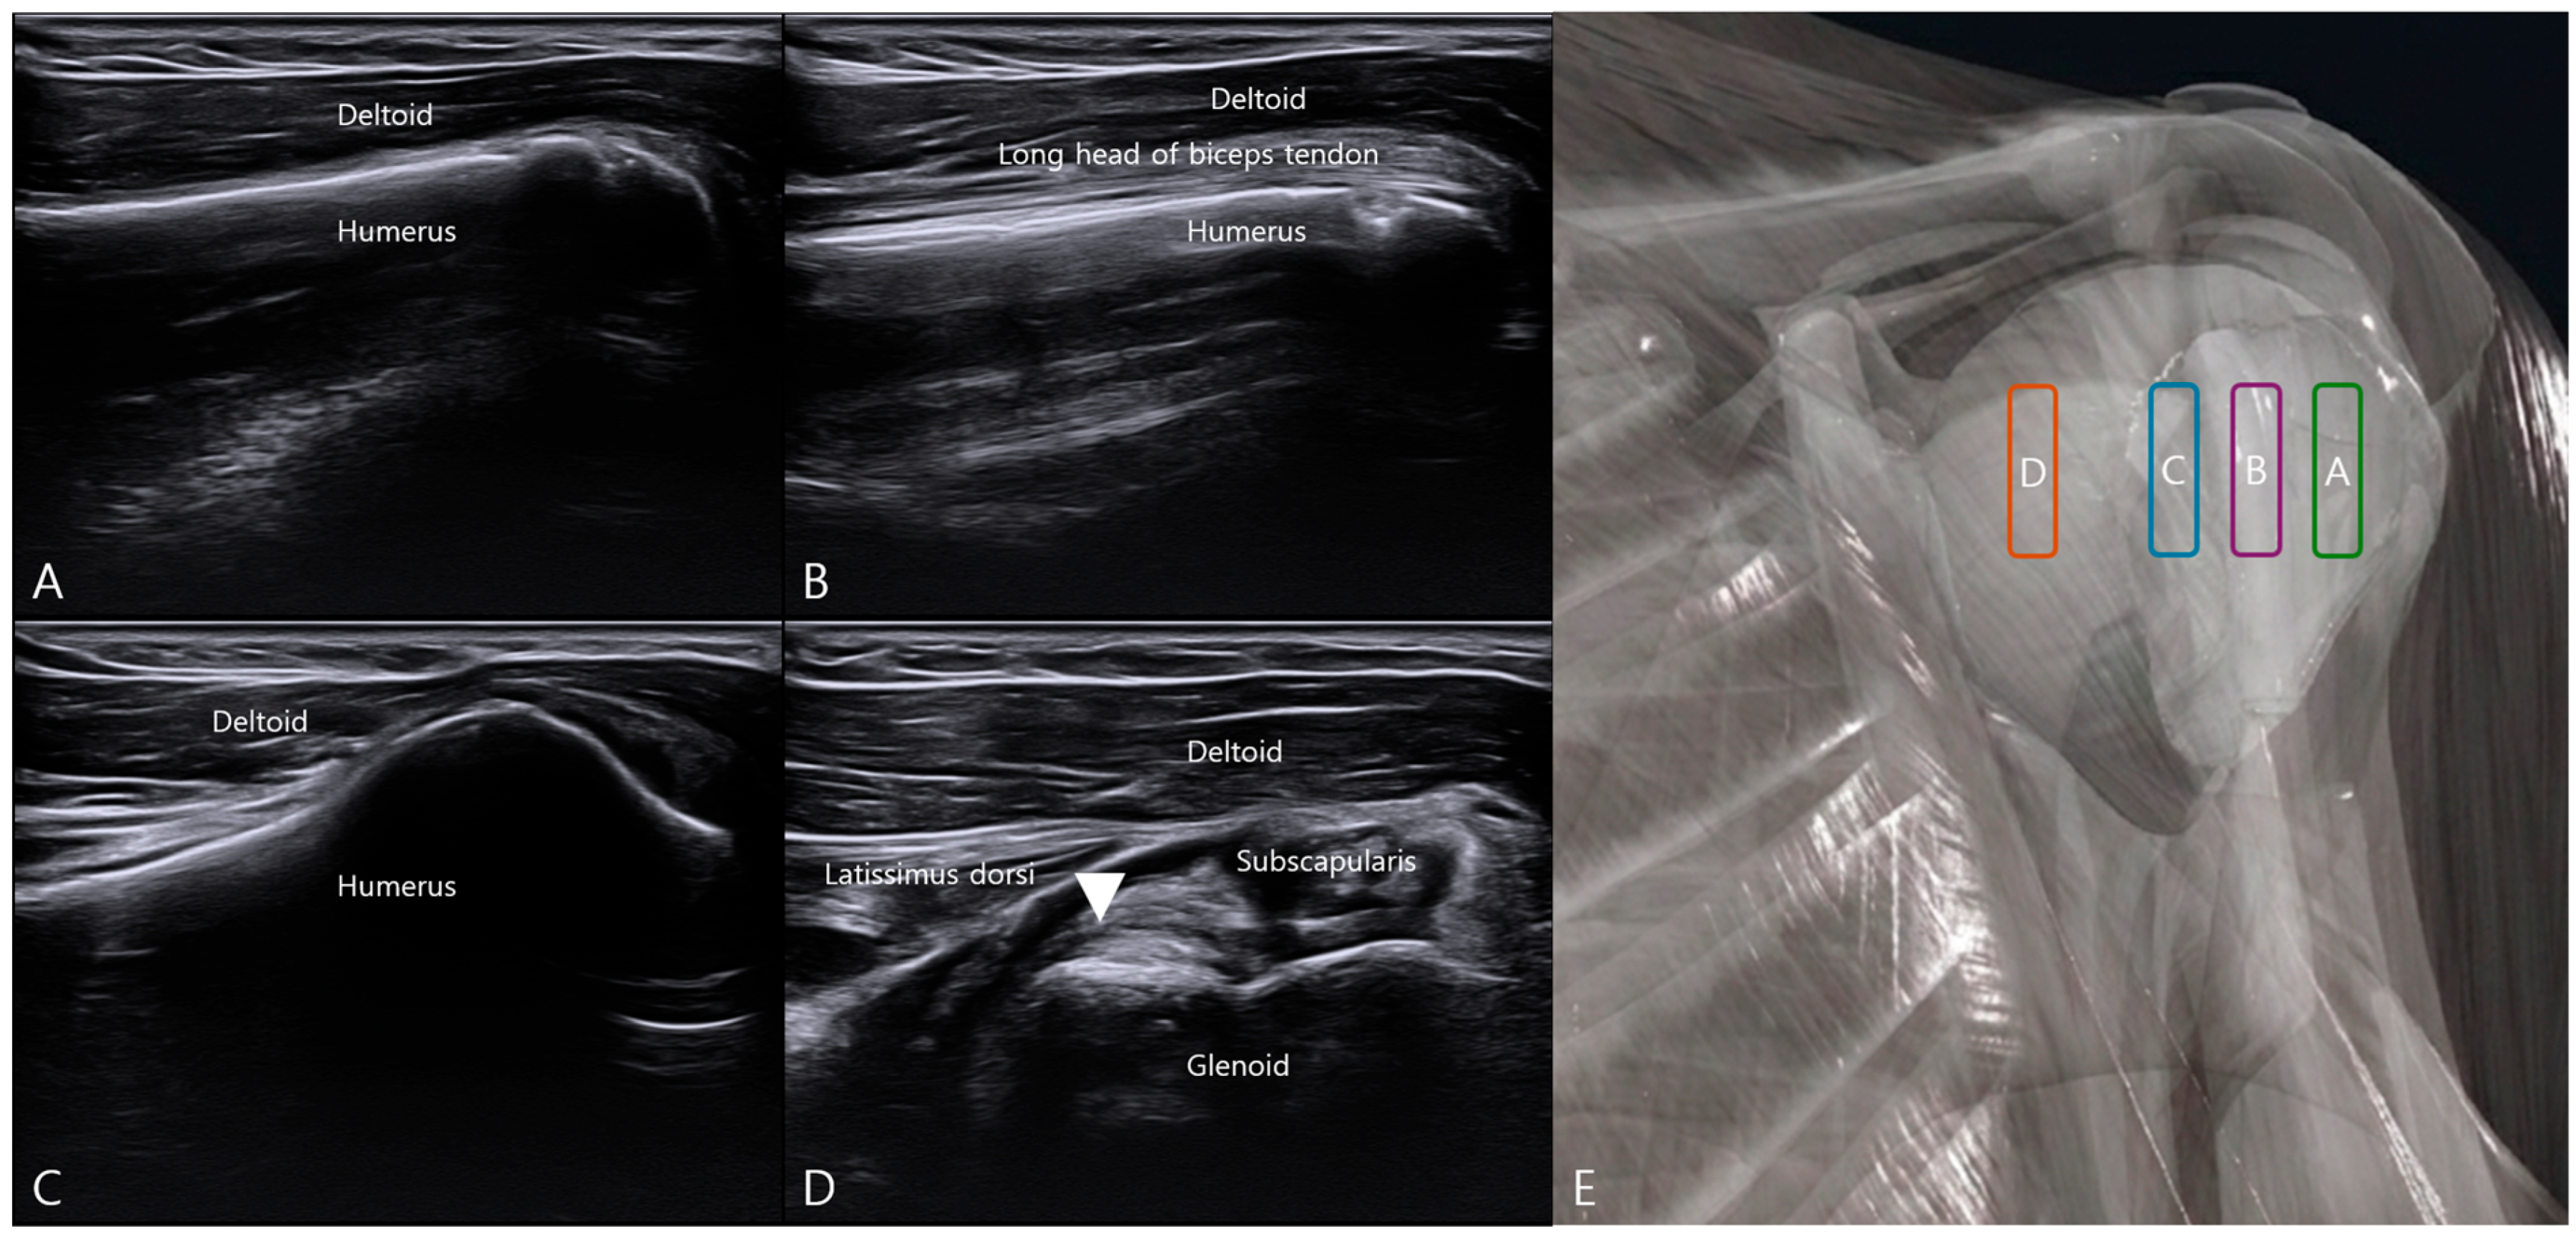

3.1. Ultrasound Landmark Identification and Localization of the ALLC

3.2. Ultrasound-Guided In-Plane Injection